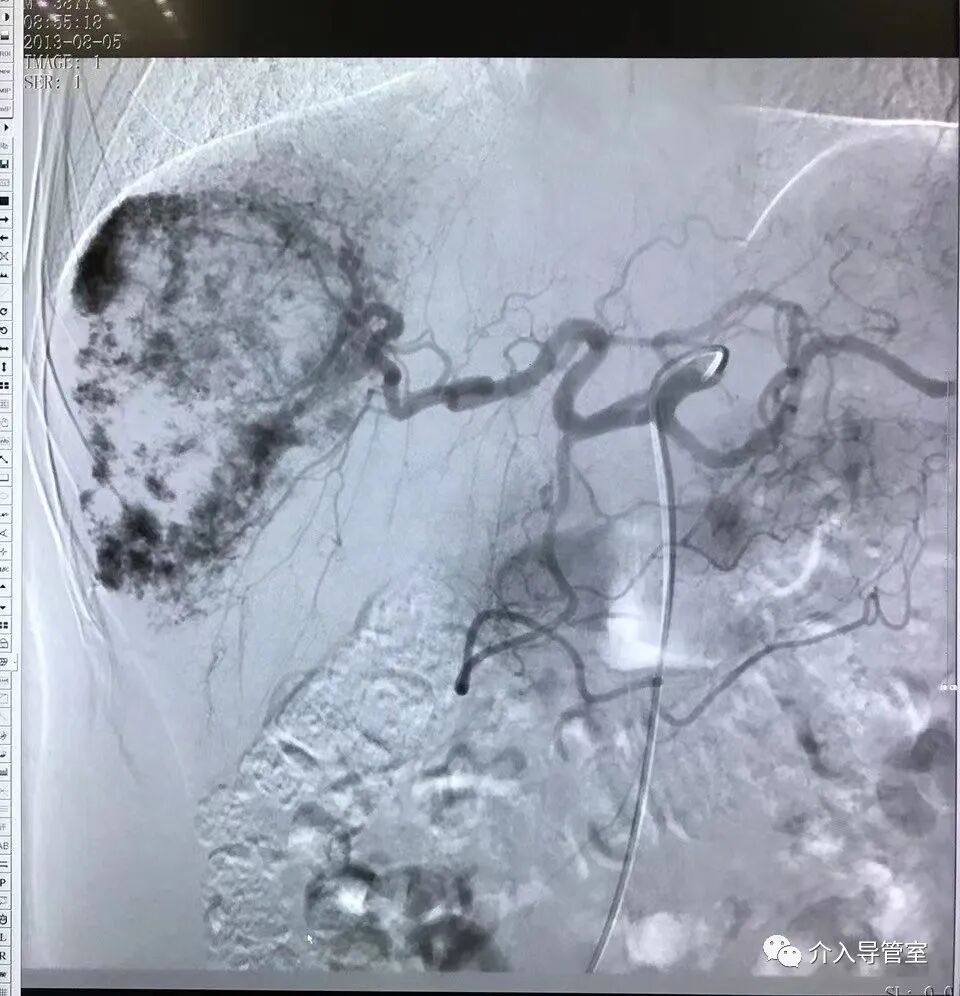

介入栓塞治疗肝血管瘤

什么是外周介入【介入科普】介入治疗在外周血管疾病中地位不可替代_https://www.jmylbn.com_新闻资讯_第3张